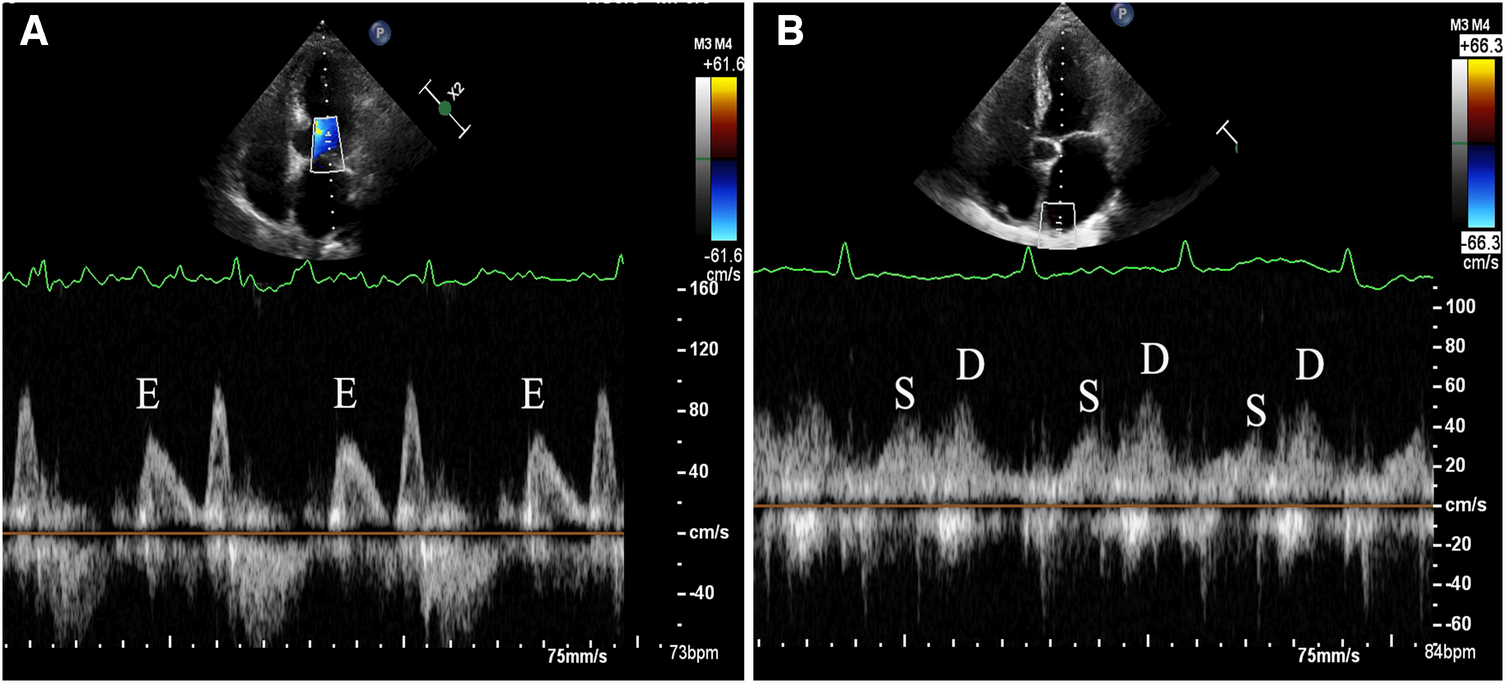

Transthoracic echocardiography (TTE) was conducted using the commercially available EPIQ 7C system (Koninklijke Philips N.V., Netherlands). The S5-1 probe with a frequency range of 1–5 MHz was utilized for the TTE examination. For TEE, the X8-2t probe with a frequency range of 2–8 MHz was employed. The time gap between the TEE and TTE should not exceed 48 h to ensure consistency and reliability of the cardiac assessment findings. The standard method was used to measure the linear dimensions of the cardiac chambers. LV volumes and EFs were calculated using the modified Simpson's method, based on the apical 2 and 4 chamber views. The validated Devereux's formula was applied to calculate the left ventricular (LV) mass: LV mass = 0.8{1.04[(SWT + LVEDD + PWT)3−LVEDD3]} + 0.6, where SWT = left ventricular end-diastolic septal wall thickness, LVEDD = left ventricular end-diastolic diameter, and PWT = left ventricular end-diastolic posterior wall thickness. The biplane Simpson's method was used to measure the LA volume from the apical 2- and 4-chamber views. Afterwards, the LV mass and LA volume were normalized to the body surface area. The apical 4-chamber view was used to measure the peak velocities of the diastolic early (E) trans-mitral Doppler flow, placing the sample volume at the tip of the mitral leaflets. Tissue Doppler imaging was used to measure the e' velocity at the septal and lateral mitral annulus during peak early diastole. The E/e' ratio was then calculated by dividing E by the mean e’. The maximum inflow velocities of the LA were defined using the recorded velocity of the right upper pulmonary vein inflow during systole (S) and diastole (D), and the S/D ratio was calculated. When the patients were in AF, the echocardiographic variables, such as the trans-mitral Doppler flows, mitral annular velocity (e'), and flow in the right upper pulmonary vein, were measured during 5 consecutive cardiac cycles and subsequently averaged to obtain consistent and reliable data. When the patients were in sinus rhythm, all Doppler measurements were averaged from three measurements. The LA acceleration factor (α) (11) was defined as the ratio of E to the average of S and D (Figure 2). The calculation formula is as follows: α = E/[(S + D)/2]. After excluding all contraindications for TEE examination, a detailed explanation of the procedure was provided, and written consent was obtained from all patients prior to undergoing the TEE examination. A thrombus within the LA was characterized as a well-defined, uniformly dense mass, distinct from the surrounding LA endocardium and pectinate muscles. It was observed in multiple imaging planes. Additionally, smoke-like echocardiographic findings with swirling blood flow in the LA and/or left atrial appendage, referred to as SEC, were identified even when gain settings were optimally adjusted. SEC is recognized as a marker of potential thromboembolic events, and is indicative of a hypercoagulable state. All measurements were carried out and interpreted by experienced physicians who were blinded to the objectives of the study to maintain an unbiased assessment.

Figure 2

Demonstration of measurement method for left atrial acceleration factor (α) by transthoracic echocardiography. (A) The apical 4-chamber view was used to measure the peak velocities of the diastolic early (E) trans-mitral Doppler flow, placing the sample volume at the tip of the mitral leaflets. (B) The maximum inflow velocities of the LA were defined using the recorded velocity of the right upper pulmonary vein inflow during systole (S) and diastole (D).